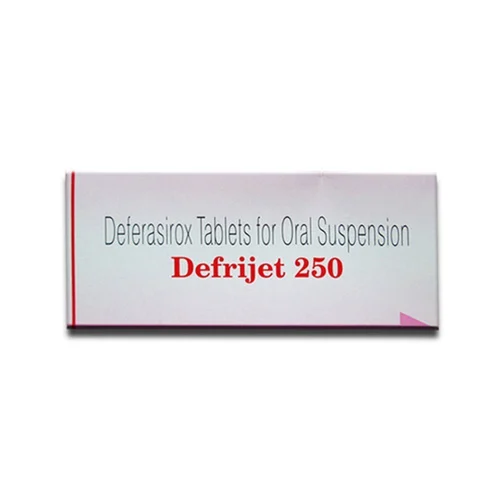

Trending products